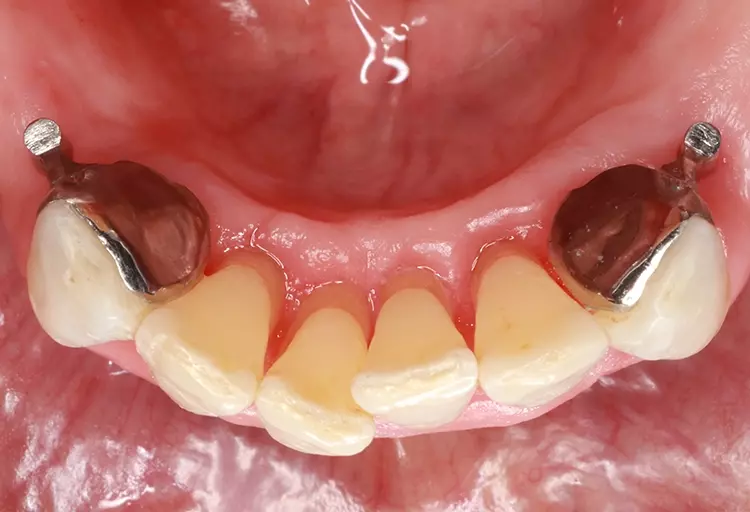

Als relative Kontraindikation sind karies- und restaurationsfreie Pfeilerzähne mit zervikalen keilförmigen Defekten über 1 mm Tiefe zu nennen, da diese zu einer erhöhten Frakturgefahr des Pfeilerzahnes bei Belastung führen. Adhäsivattachments können zur Reparatur vorhandener Doppelkronen- oder Geschiebearbeiten verwendet werden, sofern der verbliebene Nachbarzahn einer verloren gegangenen Doppelkrone karies- und restaurationsfrei ist. Die Matrize wird in diesem Fall in die ausgeschliffene Doppelkrone oder in die Geschiebekrone des verlorenen Pfeilerzahns eingeklebt (Abb. 1 bis 4).